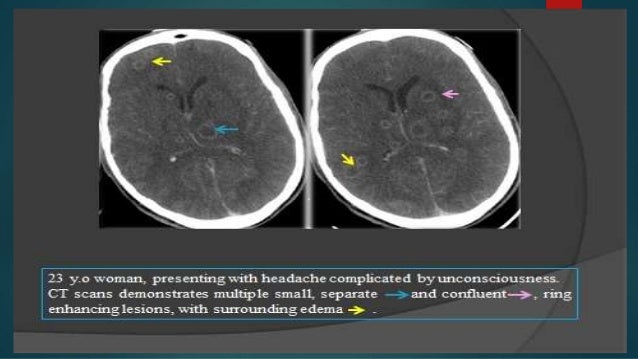

In patients with cerebral mass lesions neuroimages typically show one or more ring enhancing lesions involving both gray and white matter the cerebellum and the brain steam. Is a three dimensional lesion that occupies a space within the breast. Pre contrast t1w mri.

5658 magnetic resonance imaging mri and cranial computed tomography ct reveal single or multiple tumor like lesions with hypodense or hypointense centers with or. The first step is to determine whether the lesion presented on the ct scan is ring enhancing or non enhancing. If it is a ring enhancing lesion the most commonly seen etiologies are cerebral toxoplasmosis 50 primary central nervous system cns lymphoma 30 less commonly bacterial or fungal abscess eg.

A ring enhancing lesion is an abnormal radiologic sign on mri or ct scans obtained using radiocontraston the image there is an area of decreased density see radiodensity surrounded by a bright rim from concentration of the enhancing contrast dyethis enhancement may represent breakdown of the blood brain barrier and the development of an inflammatory capsule. The differences between enhancing and nonenhancing lesions in mri are obvious.